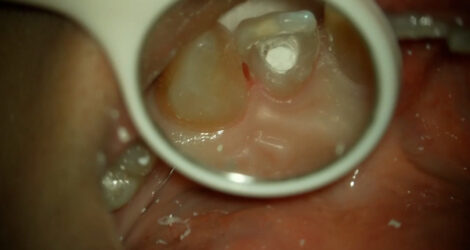

虫歯除去&MTA

こんにちは!歯科衛生士の吉村です

今回は虫歯除去とMTAについての症例をご紹介いたします。

20代男性 過去にレジンで治療した箇所が痛みはないが二次的虫歯になっていました。

虫歯除去した後今の現状や虫歯の大きさを3Dスキャナーで撮影しどう処置をしていくかお話しさせて頂きました。

【術前】↓